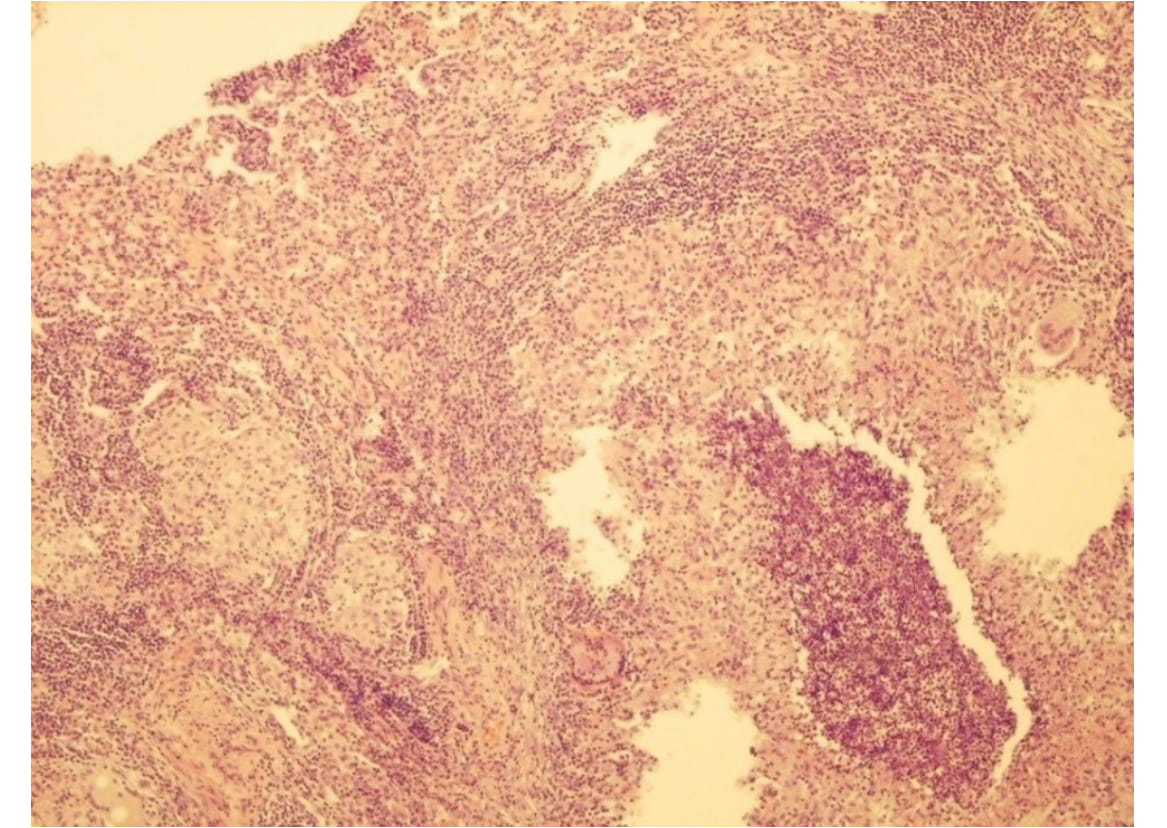

Patient G., 32 years of age, suffering from fibro-cavernous tuberculosis of the right lung in the phase of progression (Fig. 1) has been treated for 6 months conservatively with no effect, multiple drug resistance of Mycobacterium tuberculosis was detected. Pneumonectomy was performed, which revealed enlarged indurated and adherent to the surrounding tissues paratracheal, subcarinal and periesophageal lymph nodes (Fig. 2). Mediastinal lymphadenectomy was performed. On the cross-section of lymph node massive caseation was found (Fig. 3). Morphological analysis showed the presence of dry amorphous detritus with lymphoid elements and of single epithelioid cells in the peripheral areas (Fig. 4).

Fig. 4. Dry amorphous detritus with lymphoid elements and single epithelioid cells in the peripheral areas. Staining with hematoxylin and eosin. х150